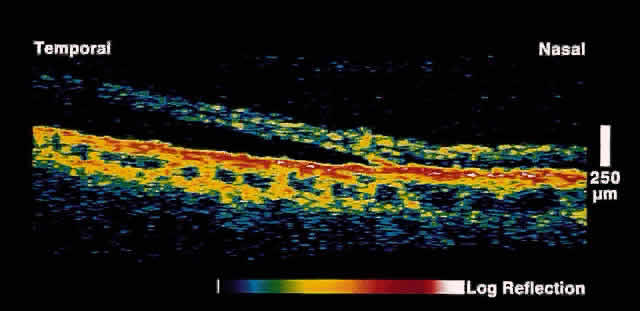

By measuring the echo delay of various intraocular structures, a translated axial image similar to A-mode ultrasonography is produced. When successive axial measurements at different transverse points are combined, a tomographic or cross-sectional image of tissue is obtained. OCT images are displayed in false-color to enhance differentiation of structures. Bright colors (red to white) correspond to tissues with high relative optical reflectivity, whereas darker colors (blue to black) correspond to areas of minimal or no optical reflectivity. Cursors may be placed on the image to give exact measurements to the nearest micron. The image produced is enlarged by a factor of two in the vertical direction for better image readability; this may in some cases distort the image (e.g., exaggerate the depth of the nerve cup).

Initial studies using postmortem eyes showed good correlation between OCT images and histologic sections. Subsequent in vivo analysis demonstrated the ability of OCT to image the substructure of the retina. Figure 1 shows an OCT image of a normal fovea and optic disc taken along the papillomacular axis. Anatomic features such as the fovea, optic disc, and retinal profile are evident. The vitreoretinal interface is noted by the contrast between the nonreflective vitreous and the reflective surface of the retina. The foveal center demonstrates normal retinal thinning and has a characteristic pit to its contour. The optic disc demonstrates normal nerve head contour and cupping. The retinal nerve fiber layer, inner plexiform layer, outer plexiform layer, photoreceptor layer, choroid, and sclera are all well delineated.

Fig. 1. Color photograph of normal fundus. The white line indicates the area of retina and optic disc scanned on the corresponding OCT in B. B. OCT image through papillomacular bundle shown in A. The vitreoretinal interface, individual retinal layers, choriocapillaris, foveal contour, and optic disc are well delineated.

The posterior aspect of the neurosensory retina is bounded in the OCT images by a highly reflective red layer about 70 microns thick that represents the choriocapillaris and retinal pigment epithelium (RPE) layer. In vivo choriocapillaris thickness by OCT is greater than that of histologic sections because of postmortem blood depletion and artifacts in tissue processing. The high contrast between the choriocapillaris/RPE layer and the neural retina in OCT images provides a useful boundary for use in measurements of retinal thickness. Retinal blood vessels are evident in OCT images by their shadowing of deeper retinal structures. The region just anterior to the choriocapillaris/RPE layer is typically weakly reflective and corresponds to the photoreceptor layer. The highly reflective red layer at the inner margin of the retina corresponds to the nerve fiber layer. In the OCT image taken along the papillomacular axis (see Fig. 1), the thickness of the nerve fiber layer increases from the fovea to the optic disc. Circular tomographs taken around the disc demonstrate modulations in thickness consistent with the superotemporal and inferotemporal bundling of the nerve fibers. Because retinal detail is so exquisitely imaged by OCT, this imaging modality can be applied to a large number of clinical entities.